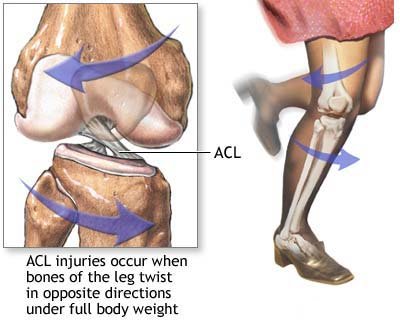

ACL Rupture

Football is the commonest cause, but any injury with full weight over a twisted knee can cause an ACL rupture.